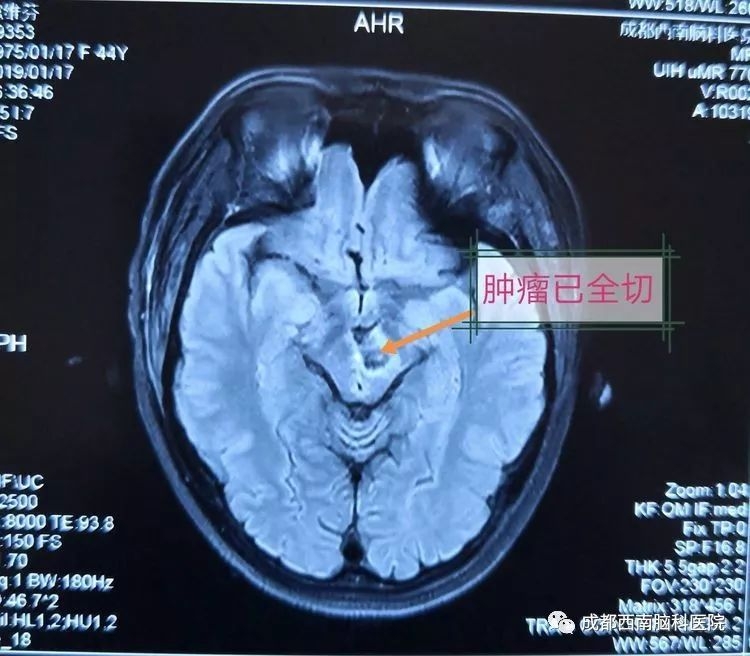

这样的情况下,她以“视物模糊伴重影18天,加重伴左眼睑下垂3天”入成都西南脑科医院。入院查体见左侧动眼神经麻痹,余未见异常。MRI检查显示,扈女士颅内的肿瘤位于中脑上端,经大脑向同侧丘脑发展,血管成像肿瘤显影良好,初步诊断为脑干肿瘤,海绵状血管瘤可能性大。

术后复查MRI显示已全部切除